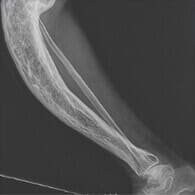

Eltörtem a lábam, és nagyon sokáig voltam kórházban rándulással, a szakember azt mondta, hogy járni fogok, de hozzá kell szoknom az időnkénti fájdalomhoz. Azonban kibírhatatlan volt a fájdalom, minden lépés olyan volt, mint egy megpróbáltatás. Az ízületek helyreállításához elkezdtem a lábamat Remofixnel kenni. A fájdalom azonnal alábbhagyott, remélem, hamarosan teljesen elmúlik.